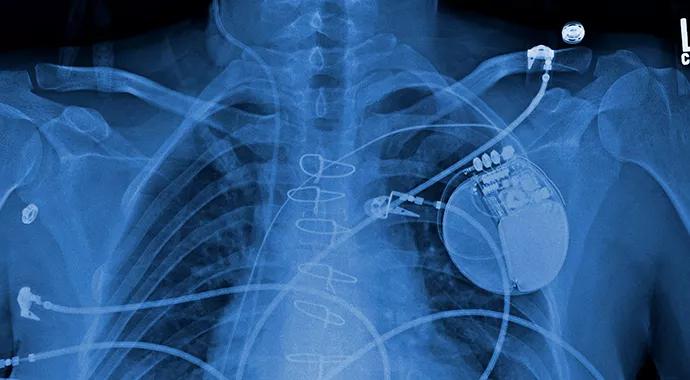

Despite maximum medical therapy, Logan’s heart failure worsened. At this point, his cardiologists believed he might benefit from a left ventricular assist device (LVAD).

Three LVADs are available for pediatric patients. All require careful management of anticoagulation.

Logan was given a third-generation HeartWare® VAD. He began to gain lean body mass almost immediately and was able to begin physical therapy. As a result, he was in good condition to tolerate the transplant when a donor heart arrived six weeks later.